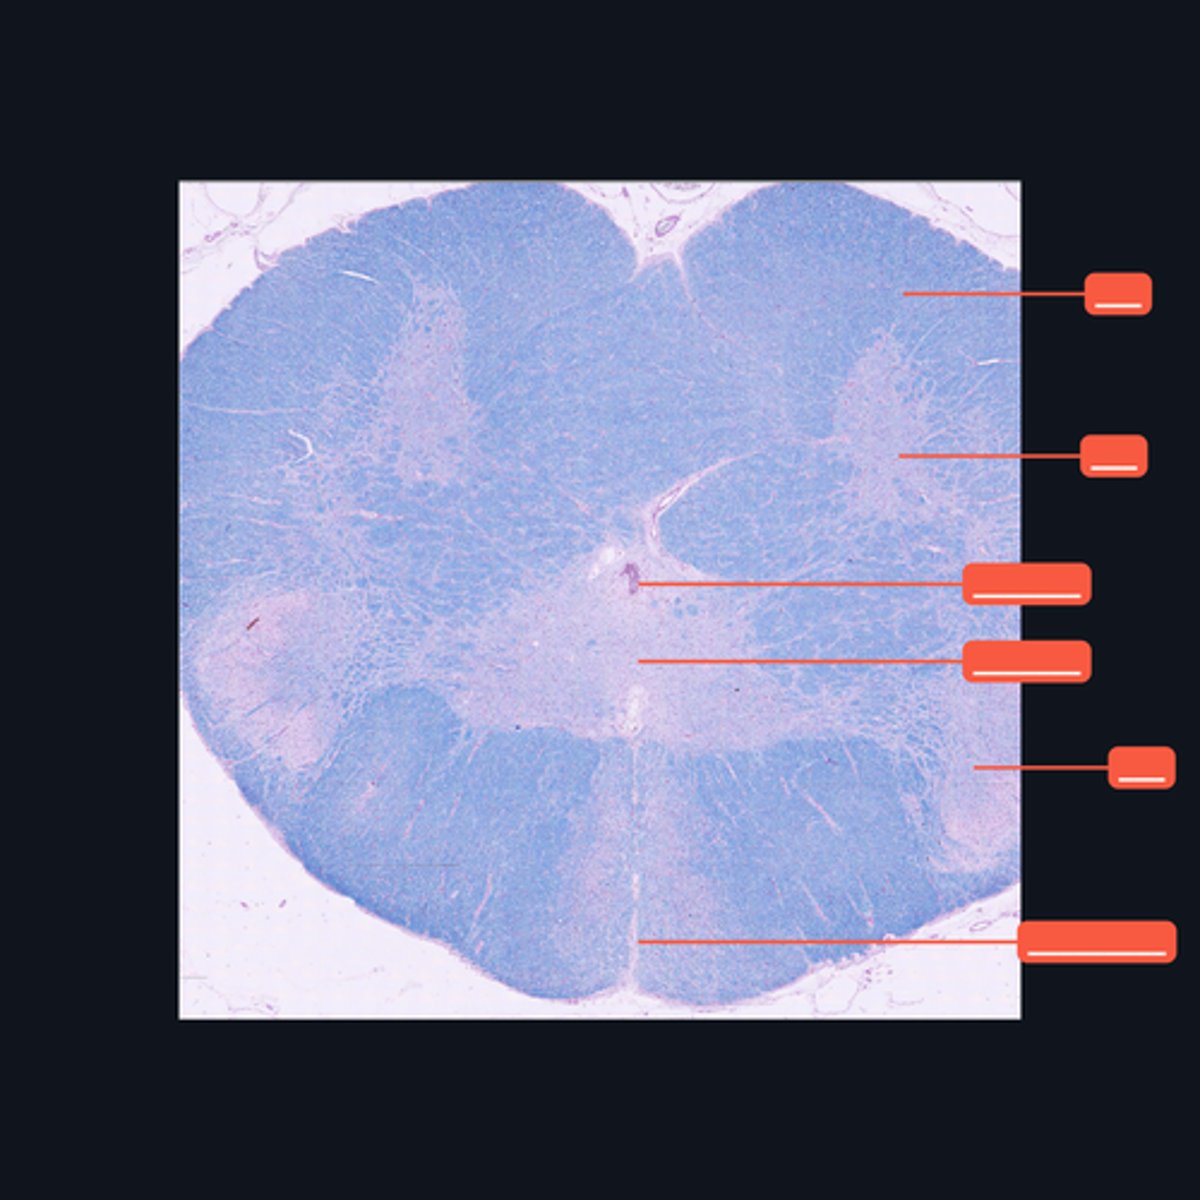

Identify the pointed region in the Cerebellum

Folia

The surface of the cerebellum exhibits transverse folds called the _____.

Purkinje cells

This middle layer of the cerebellar cortex consists of a single layer of pear-shaped multipolar neurons called _____.

Granule cells

The layer is densely populated by small, round to oval neurons called _____.